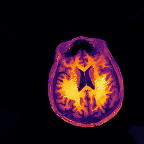

Multi-modality (or multi-channel) imaging is becoming increasingly important and more widely available, e.g. hyperspectral imaging in remote sensing, spectral CT in material sciences as well as multi-contrast MRI and PET-MR in medicine. Research in the last decades resulted in a plethora of mathematical methods to combine data from several modalities. State-of-the-art methods, often formulated as variational regularization, have shown to significantly improve image reconstruction both quantitatively and qualitatively. Almost all of these models rely on the assumption that the modalities are perfectly registered, which is not the case in most real world applications. We propose a variational framework which jointly performs reconstruction and registration, thereby overcoming this hurdle. Numerical results on simulated and real data show the potential of the proposed strategy for various applications in multi-contrast MRI, PET-MR, and hyperspectral imaging: typical misalignments between modalities such as rotations, translations, zooms can be effectively corrected during the reconstruction process. Therefore the proposed framework allows the robust exploitation of shared information across multiple modalities under real conditions.

翻译:多模式(或多通道)成像越来越重要,而且越来越普及,例如遥感中的超光谱成像、材料科学中的光谱CT以及医学中的多调MRI和PET-MR等,过去几十年的研究产生了大量数学方法,将多种模式的数据结合起来。通常作为变异性正规化的先进方法表明,在数量和质量上都大大改进了图像重建。几乎所有这些模型都基于这样一种假设,即模式已经完全登记,而在大多数现实世界应用中情况并非如此。我们提议了一个变通框架,共同进行重建和登记,从而克服这一障碍。模拟和实际数据的数字结果显示,拟议的多调MRI、PET-MR和超光谱成像的各种应用战略具有潜力:在重建过程中可以有效地纠正诸如轮换、翻译、缩影等模式之间的典型的不匹配。因此,拟议的框架允许在现实条件下,在多种模式中大力利用共享的信息。